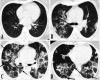

Is target sign (bull’s eye appearance) associated with adverse outcomes in COVID 19 patients? A case series and literature review

Background: In COVID-19 pneumonia, chest CT scan plays a crucial role in diagnosing and closely monitoring lung parenchyma. The main reportedly chest CT features of novel coronavirus pneumonia (NCP) have been fully discussed in the literature, but there is still a paucity of reports on uncommon CT manifestations.

Case presentation: Herewith, we have reported ten rRT-PCR confirmed COVID-19 patients with CT target signs (bull's eye appearance); additionally, we have reviewed previously reported cases. Reviewing the literature, we found eight COVID-19 patients with target sign in the literature. 18 patients were included with a median age of 43. 11 (61%) patients were males. In 87% of patients, the lesions developed within the second-week post symptom onset. These patients mostly experienced an extended hospital stay (median = 10 days), with 53.8% of cases being admitted in ICU. The in-hospital mortality rate was 23%.

Conclusion: Our findings indicate that lesions with a bull's eye appearance are not significantly associated with higher mortality in hospitalized COVID-19 patients.